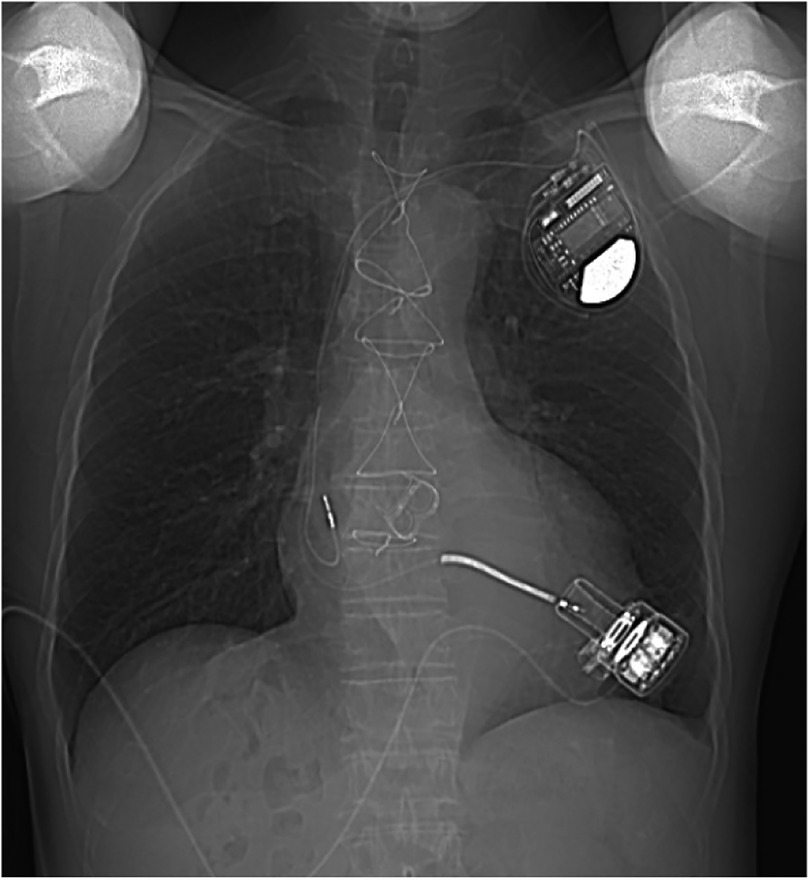

Figure 4

A chest x-ray was performed 1 year after discharge.

The patient exhibited oliguria on the first postoperative day (POD), accompanied by a rise in renal function index. The patient was placed on bedside continuous renal replacement therapy (CRRT). The patient's urine returned to a normal level on POD4. The patient was extubated on POD4. The patient had more pleural fluid postoperatively, which was deemed to be associated with exudate from the artificial vessel and the extensive surgical trauma. The drainage levels decreased, and the chest tube was subsequently removed on POD19. Heparin was administered, and the activated clotting time (ACT) was maintained at 160–200 s. The patient's warfarin was initiated on POD6, trying to maintain the international normalized ratio (INR) at 1.8–2.5. At 2 weeks postoperatively, the patient was able to ambulate and move without assistance. He was discharged on POD26 without any adverse events, while the LVAD achieved a pump flow of 3.08 L/min at 2,846 rpm. One year after the surgery, echocardiography revealed normal prosthesis function and reduced valve regurgitation, with an ejection fraction of 30% and an LVEDD of 68 mm (Figure 3). The chest x-ray taken 1 year after the patient was discharged from the hospital is shown in Figure 4.